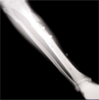

Pre Op

Xrays